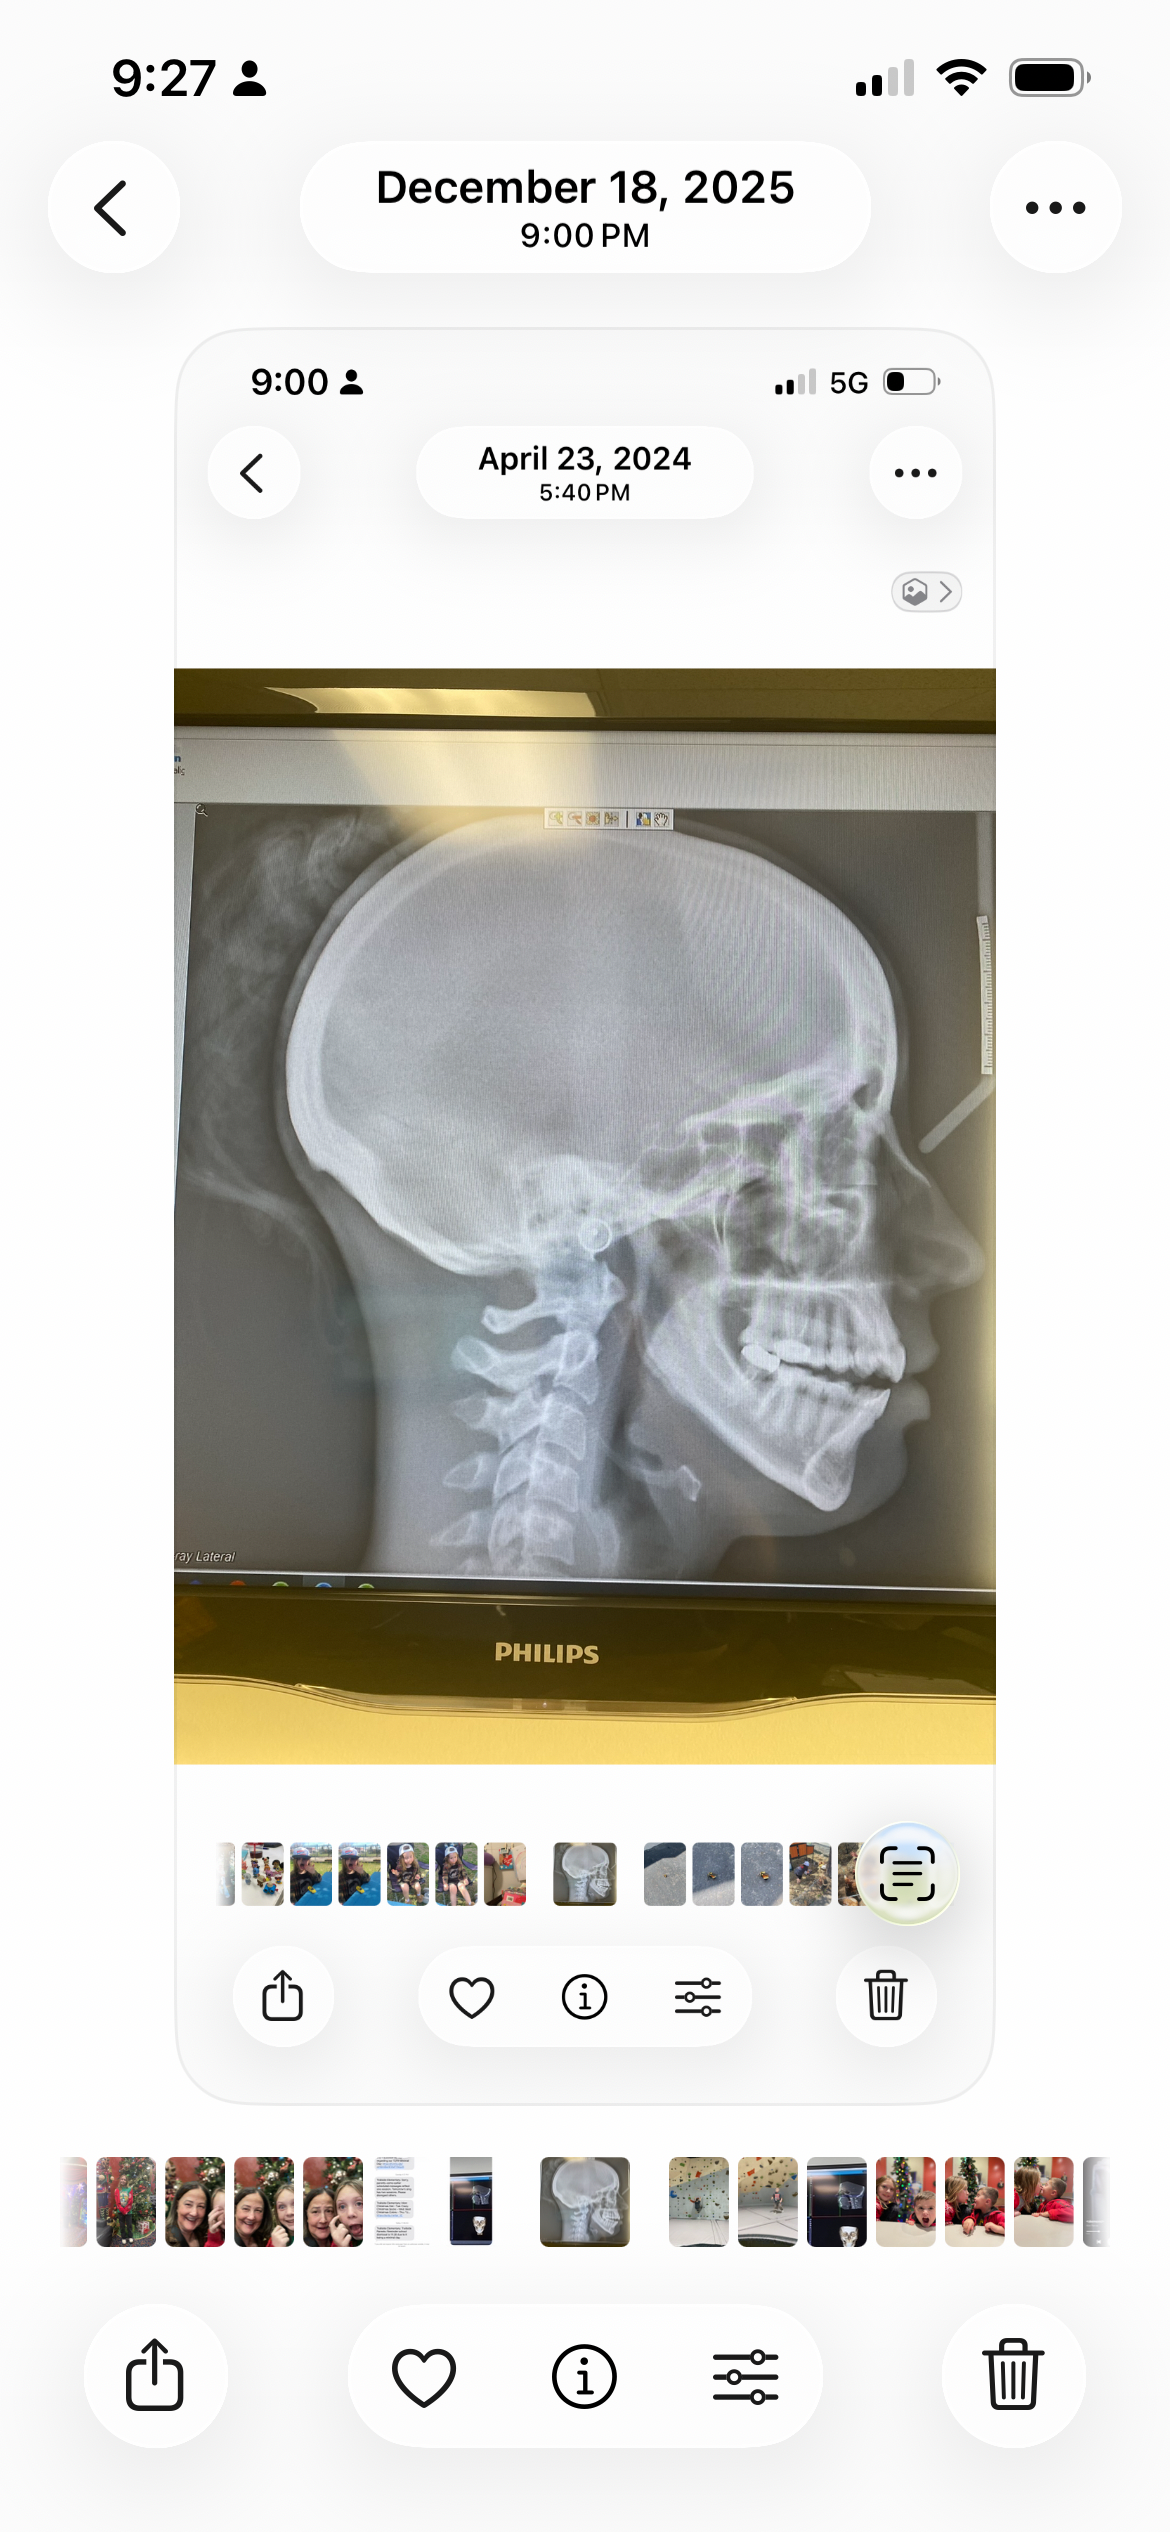

Idiopathic Condylar Resorption or "ICR" is an unexplained degenerative disease of the temporomandibular joint (TMJ) that leads to the destruction of the mandibular condyles. The mandibular condyle is the bone that connects your mandible to your skull and is responsible for providing stability to support jaw movement. When bone loss occurs, the jaw retracts back, resulting in an open bite, recessed jaw, and a variety of chronic symptoms that negatively impact quality of life. Below is a short video about ICR.

Right now, my bite is very unstable, and only the molar at the very back on the left side touches, which limits what I can eat. I am one of the lucky ones who is still able to eat; however, I now have many limitations on what I can safely eat. My pain is manageable some days. Other days, I am happy to make it through the day and come home to my heating pad for some relief. The recession of my jaw has caused severe neck pain, narrowing of my airway, and changes to my facial appearance. The worst part of having ICR is the toll it has taken on my mental health.